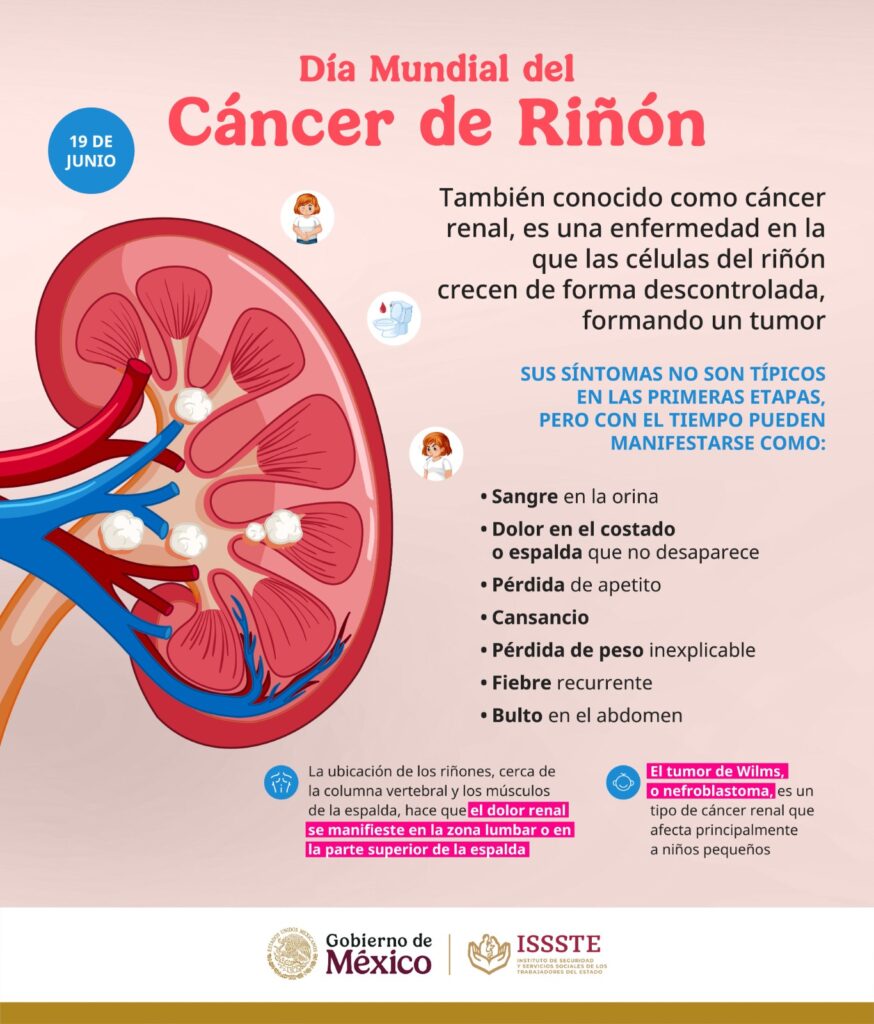

García Cárdenas subrayó que, de todos los cánceres conocidos, este afecta más a hombres que a mujeres por factores como condiciones genéticas, exposición a ciertos metales pesados, hipertensión arterial, obesidad y tabaquismo. Además, comentó que en ocasiones esta enfermedad no causa síntomas; no obstante, cuando crece, las personas pueden presentar sangre en la orina, dolor en la espalda, pérdida de peso sin razón aparente, fiebre, hinchazón de piernas y tobillos.

“Cursan asintomáticos porque la persona puede no tener ningún signo y síntoma, pero buscando un poco, pudiera haber sangrado en la orina o inclusive puede no sentirse. Por otro lado, puede sentir esa persona un bulto en la zona abdominal, en la zona lumbar, incluso, puede pasar que no quiera comer, o anemia. Cuando estos datos se presentan lo más recomendable es empezar con un protocolo de estudio, sobre todo cuando una persona tiene algunos factores de riesgo”, aseveró.

Concluyó que la importancia de celebrar el Día Mundial del Cáncer de Riñón es concientizar a la población de todos los signos y síntomas de la enfermedad, y cuáles son los factores de riesgo que pueden conllevar al padecimiento.